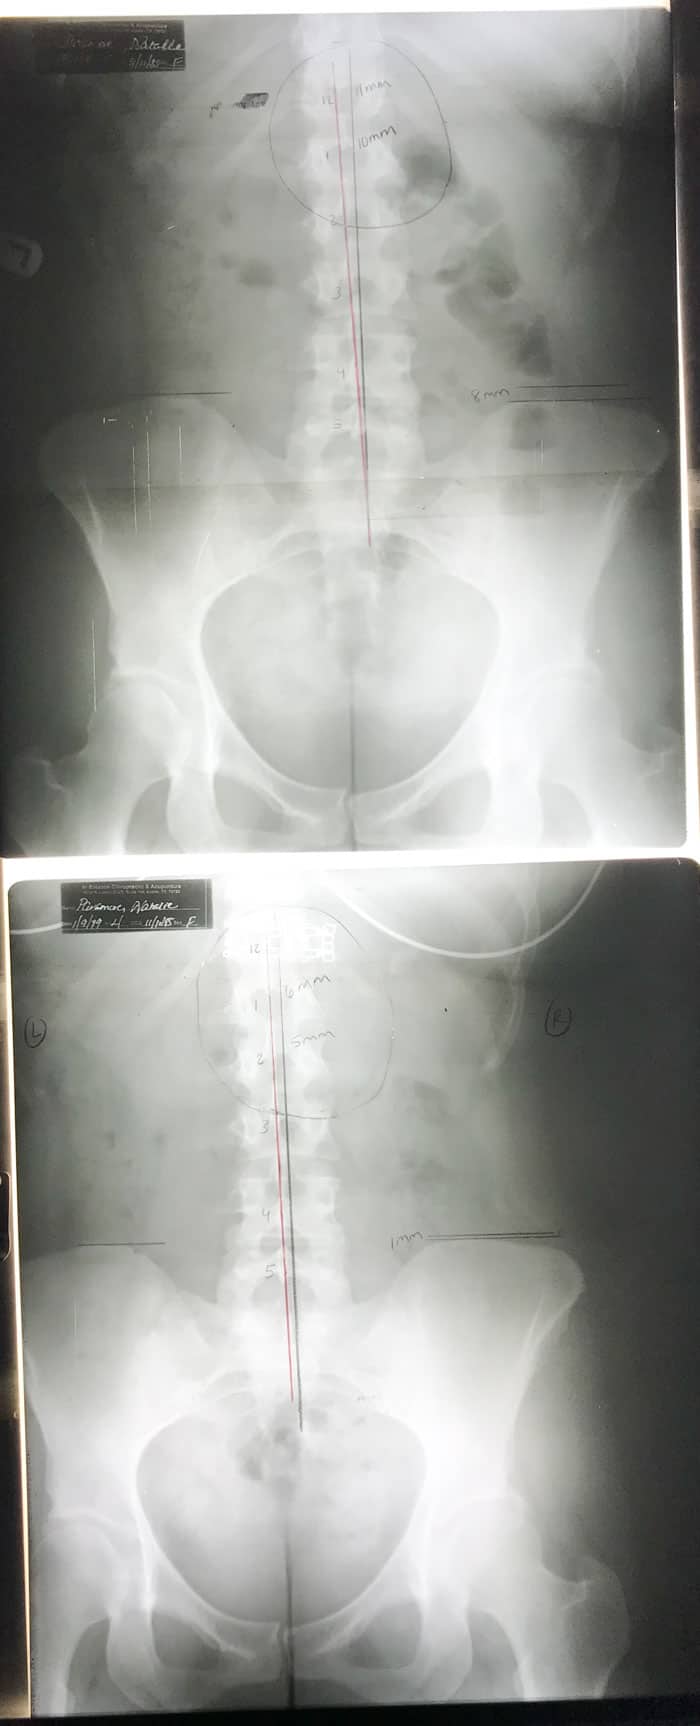

The top is the x-ray from my initial visit showing the curve of my scoliosis and the uneveness of my hips. The bottom is after one month of treatments. The black lines are where things should be and the red lines are where my body lines up.

The scoliosis was a mild curve which is most likely why it went undiagnosed my whole life. It was pulling my lower spine and hips up on one side and causing my muscles to be very tight in the lumbar area of my back and torso. This resulted in my legs being uneven by almost an inch! I always stood towards one side or swayed a lot when I was on my feet and realized this was my body compensating for my legs being so uneven. Fun fact: people usually don’t have a limp until their legs are 3 inches different in length.

After the first month, we redid the tests and x-rays and they revealed that I had gained a lot of strength back in my arms and was able to lift more weight. My shoulders were also much more flexible! The scoliosis saw a 50% improvement in the curve in just one month! My legs were almost completely even too. The best news was the my neck curve saw an almost 50% improvement as well! We both couldn’t believe it! Usually necks can take a lot of time to heal. My neck is now straight, which is still a problem, so we are going to continue working on it but needless to say, we are seeing great results!